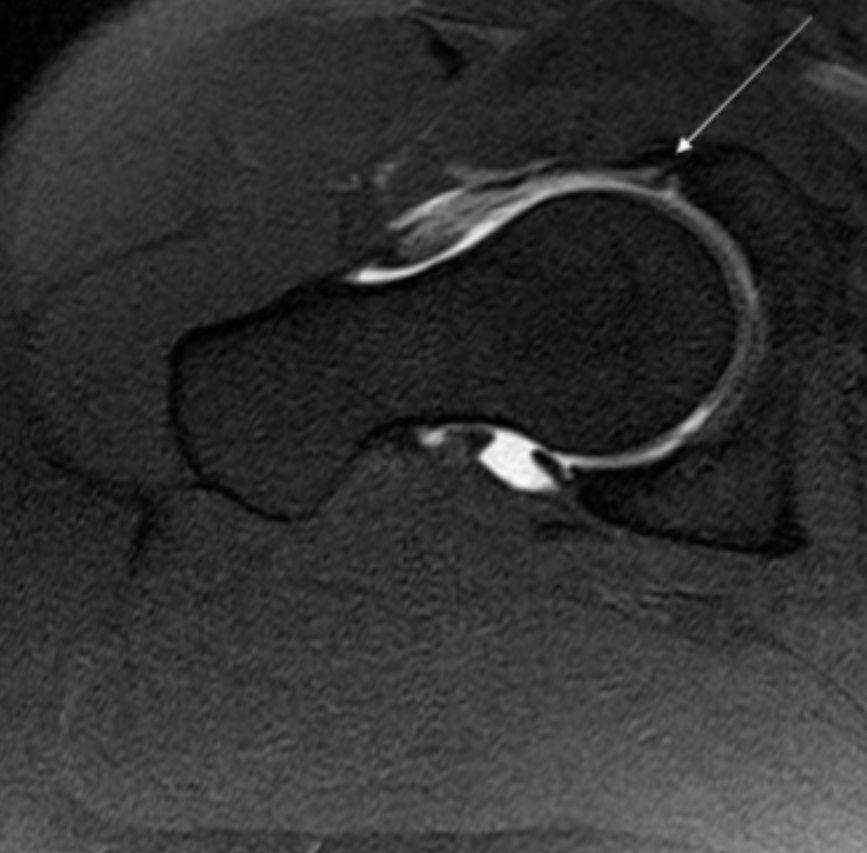

Describe the pathology indicated by the arrow (Ax T1 FS).

Labral tear

Describe the pathology indicated by the arrow (Cor T1).

AVN

Describe the pathology (hint: it’s bone) (Ax T1 FS +C).

Osteochondroma

Describe the pathology indicated by the arrow (Cor T2 STIR pelvis).

Trochanteric bursitis